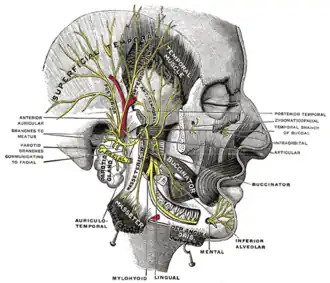

Mandibular division of the trigeminal nerve. (Inferior alveolar labeled at bottom right.) | |

The inferior alveolar nerve (IAN) (also the inferior dental nerve) is a sensory[1] branch of the mandibular nerve (CN V3) (which is itself the third branch of the trigeminal nerve (CN V)). The nerve provides sensory innervation to the lower/mandibular teeth and their corresponding gingiva as well as a small area of the face (via its mental nerve).

After branching from the mandibular nerve, the inferior alveolar nerve passes posterior to the lateral pterygoid muscle. It issues a branch (the mylohyoid nerve) before entering the mandibular foramen[2]: 543 to come to pass in the mandibular canal within the mandible. Passing through the canal, it issues sensory branches for the molar and second premolar teeth; the branches first form the inferior dental plexus which then gives off small gingival and dental nerves to these teeth themselves.[3]

Branches

Mental nerve

The mental nerve emerges from the mandibular canal through the mental foramen[1] and provides sensory innervation to the chin and lower lip.

Incisive branch

The incisive branch represents the anterior continuation of the inferior alveolar nerve. It continues to course within the mandible in the mandibular incisive canal either as a single nerve or by forming the incisive plexus. It provides sensory innervation to the lower/mandibular premolar, canine, incisor teeth as well as their associated gingiva.[1]

Distribution

The inferior alveolar nerves supply sensation to the lower teeth,[2]: 519 and, via the mental nerve, sensation to the chin and lower lip.

The mylohyoid nerve is a motor nerve supplying the mylohyoid and the anterior belly of the digastric.